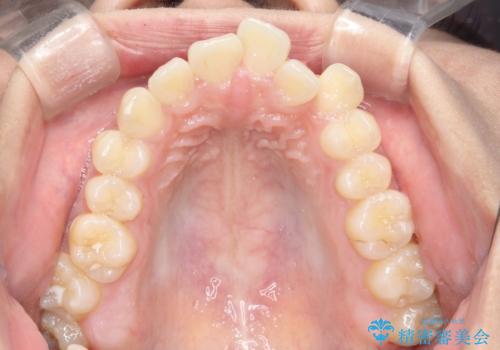

- 前歯の凸凹を主訴に来院されました。

小臼歯抜歯(上顎4番)して矯正治療を行なったことで、口元もスッキリしました。